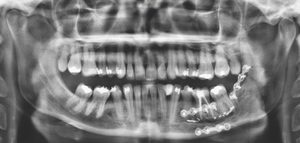

Radiographic examinations consisted of digital orthopantomogram (OPG), peri-apical (PA), and cone beam computed tomography (CBCT) scans. The scans revealed that the lower left first molar root canals were obturated with a radiopaque material, and showed root canal filling extending beyond the apices of the tooth and approximately 5cm along the mandibular canal (Figures 1, 2 and 3).